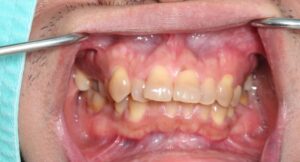

Der Therapieablauf beginnt mit einer gründlichen Funktionsanalyse von Kiefer, Zunge und der gesamten Körperhaltung. Hierfür werden auch detaillierte diagnostische Abformungen und Fotos erstellt.

Kieferorthopädische Fehlstellungen und CMD

- Positive Effekte bei Zahnengstand, Kreuzbiss, offenem Biss